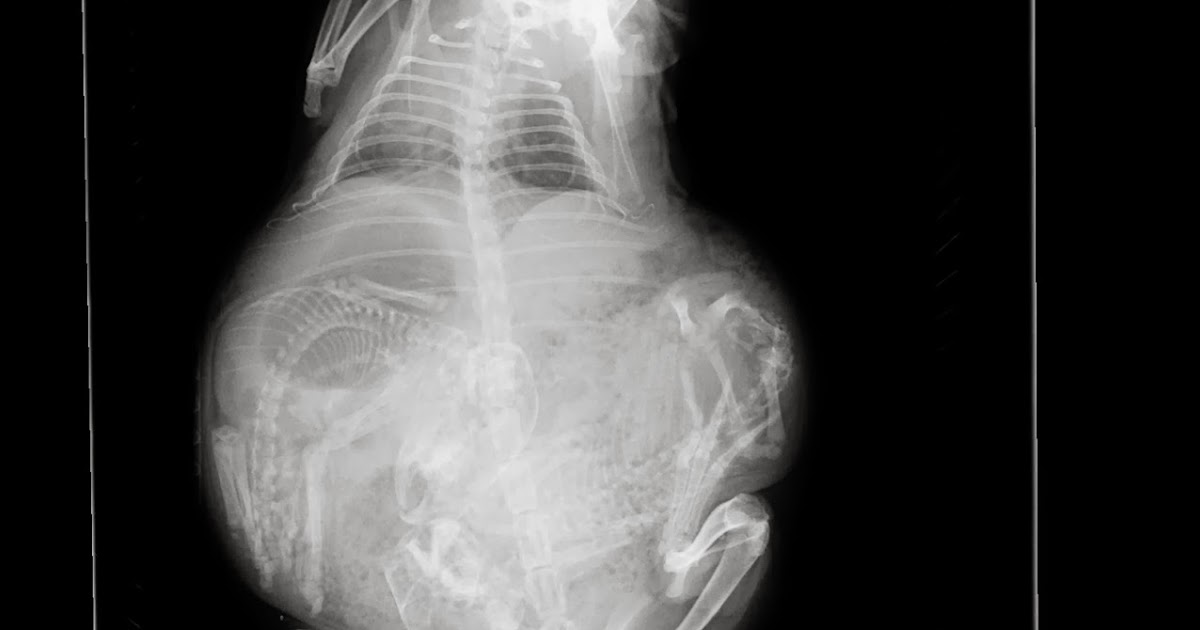

Guinea Pig Pregnancy PDF Pregnancy Pig

Guinea Pig Pregnancy Stages Of Reproduction Care Vet Approved Hepper